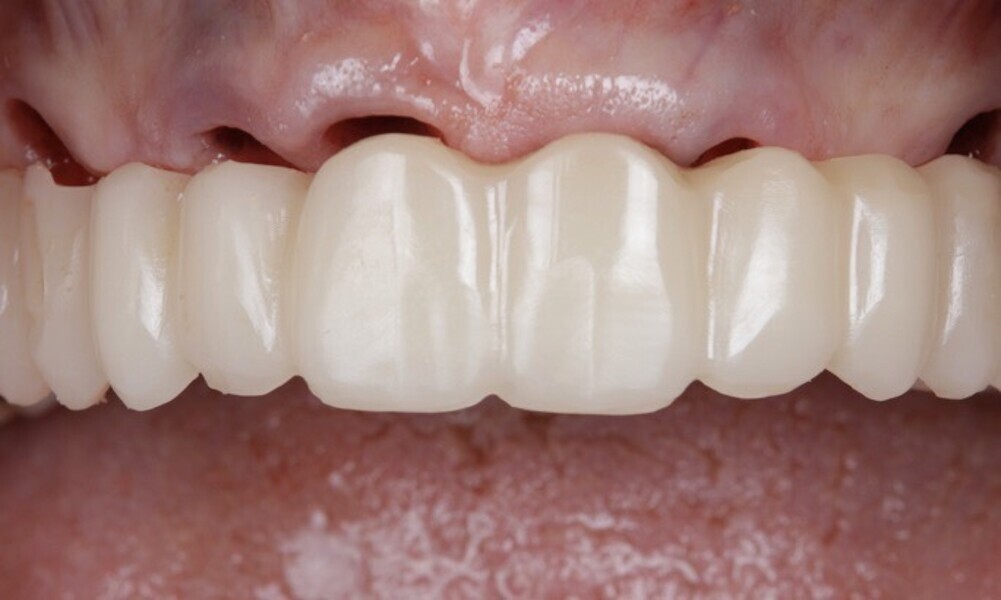

After a healing period of five months and successful osseointegration, the process for the definitive restorations was initiated. The chosen material was milled monolithic zirconia, and Variobase final abutments was used, placed on the screw-retained abutments to ensure excellent stability and retention of the definitive restorations (Figs. 69–75).

The soft tissue was in good condition, and the definitive restorations were placed (Figs. 76 & 77). After placing the definitive restorations, oral hygiene instructions were given to ensure proper care and prevent complications. Additionally, the occlusion was carefully checked and adjusted as needed (Figs. 78–83).

Figs. 78–82: The definitive restorations were placed, and occlusal adjustments were performed.